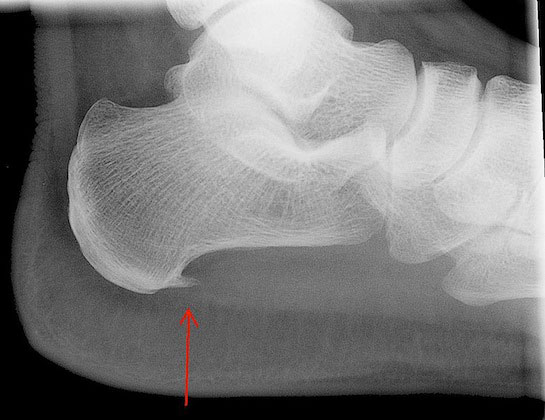

Шпоры пяток, или плантарный фасциит, представляют собой костные выросты на пятке, которые могут вызывать сильную боль при ходьбе. Врачи отмечают, что основными факторами риска являются избыточный вес, плоскостопие и чрезмерные физические нагрузки. Для диагностики шпор пяток используются рентгенографические исследования, которые позволяют визуализировать наличие костных выростов.

- Рентгенография стопы – дает отличную визуализацию на снимке костного выроста на пяточной кости. Данный метод позволяет исключить прочие патологические изменения в стопе, такие как артроз расположенных рядом суставов или же перелом пяточной кости.

Шпоры пяток — это костные наросты, которые образуются на пятках и могут вызывать дискомфорт и боль при ходьбе. Многие люди не подозревают о наличии шпор, пока не начнут испытывать неприятные ощущения. Основные симптомы включают острую боль в области пятки, особенно по утрам или после длительного сидения. Для выявления шпор обычно проводят рентгенографию, которая помогает визуализировать костные изменения.